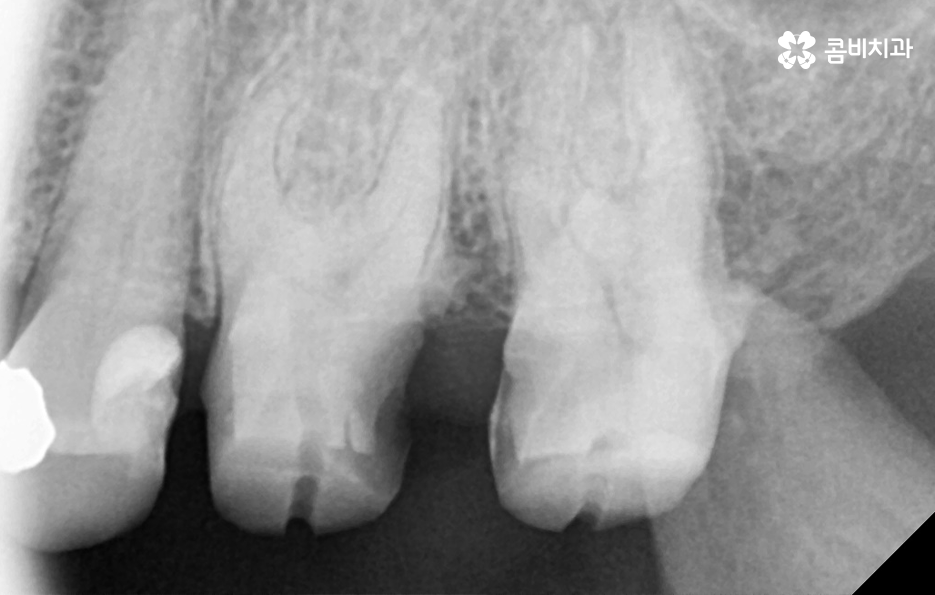

많은 환자분들께서 이미 충치 치료를 했던 부위인데 왜 또 충치가 생길 수 있는지 의아해 하시는 분들도 계실 거예요. 충치 치료를 했던 부위를 살펴보면 보철 재료와 치아 사이에 경계면이 있다는 것을 알 수 있는데요.

충치 치료 후에는 보철물과 치아 사이의 경계선 부분에서 보철물의 접착제가 녹는 경우도 있고 보철물 자체의 손상이 발생되는 경우도 있으며 보철물은 멀쩡하더라도 자연치아가 마모되고 깨지는 등의 문제가 발생될 수 있는데 이때 보철물과 치아 사이에 틈이 발생되면 치아 내부로 세균이 침투하여 2차충치가 발생되는 원리라고 할 수 있어요

이처럼 2차충치가 치아 내부로 진행된 경우에는 치아 구조의 특성상 치아의 겉면에 비해 내부가 좀더 약하기 때문에 충치는 비교적 쉽게 내부로 깊어질 우려가 있으며 신경조직에 손상이 발생한 경우에는 신경치료를 해야 하기 때문에 자연치아의 손상이 그만큼 커질 수 있어요

이러한 문제는 치아 내부에서 발생하기 때문에 눈으로 살펴볼 때는 상태 확인이 어렵고 명동치과 주기적으로 검진을 하지 않는다면 통증을 통해 뒤늦게 문제를 인지하기 때문에 치료 시점도 초기치료는 놓친 경우가 대부분이라 할 거예요

오늘 소개드린 2차충치 만큼이나 예방이 중요한 치아 문제는 치아의 인접면 즉 치아 사이에 발생한 충치라고 할 수 있는데요. 사실 2차충치나 인접면 충치 모두 기본적으로 평소 칫솔질도 잘하고 특히 치실 사용을 잘하는 것이 구강 내 세균 관리에서 평소 실천할 수 있는 구강관리 방법이며 명동치과 매년 최소 1회는 검진과 스케일링을 꼭 필수적으로 실천하는 것도 강조드리고 있어요